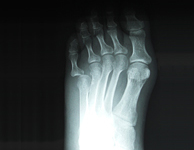

| マレットフィンガーDrに依頼施療中 | 同患者のレントゲンDr依頼により当院にて施療 | ||